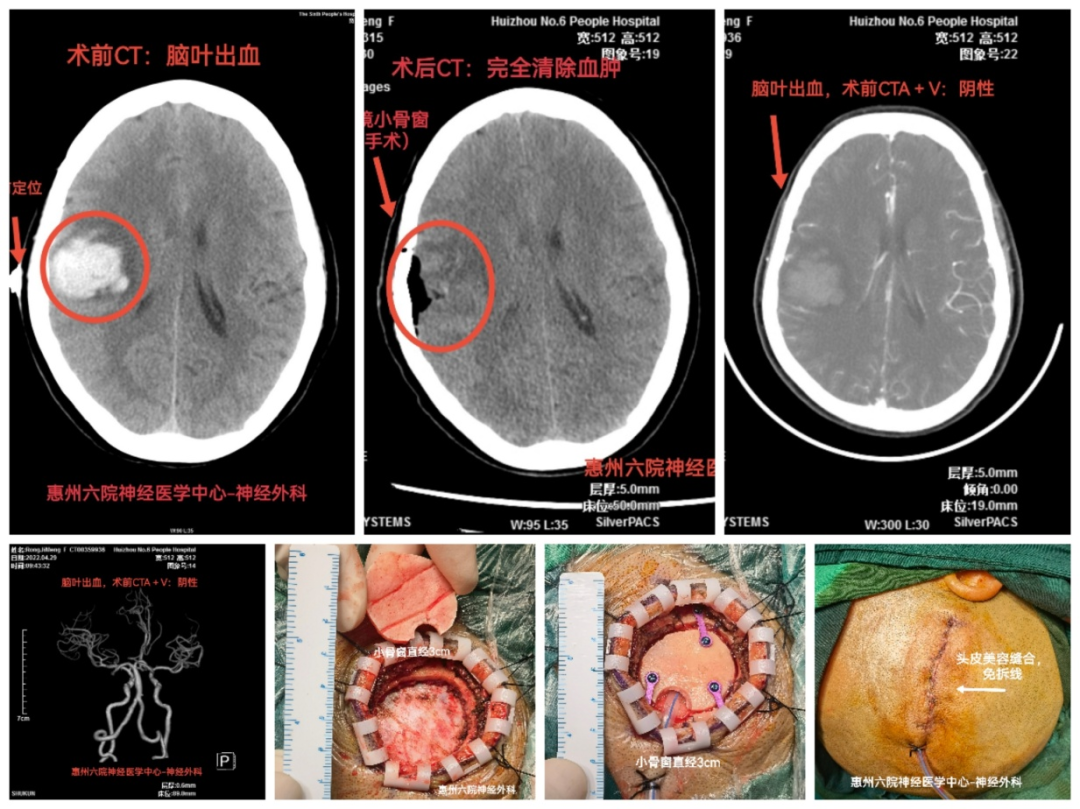

腦出血是我國(guó)居民死亡和殘疾的主要原因之一,具有高緻殘率、高死亡率、經(jīng)濟負擔重等特點,是影響群衆健康的重大疾病。以往多采用骨瓣開(kāi)顱清除血腫的辦法,創傷大、并發(fā)症多。

從2020年開(kāi)始,惠州市第六人民醫院神經(jīng)外科應用新技術——“神經(jīng)内鏡小骨窗球囊通道(dào)微創手術治療腦出血”,迅速提高腦出血的救治水平。

該項新技術,系采用小骨窗球囊通道(dào)微創方法進(jìn)入腦内血腫,在神經(jīng)内鏡輔助下清除腦内血腫。微創手術損傷小、耗時(shí)短、并發(fā)症少、成(chéng)功率高。至今已成(chéng)功開(kāi)展60多例,取得了良好(hǎo)的社會(huì)效益。